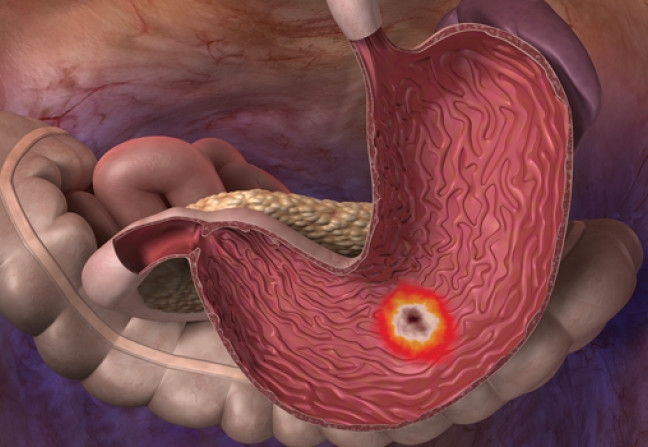

Maladie chronique fréquente, l’incidence de l’ulcère gastro-duodénal a notablement chuté depuis dix ans en raison de la découverte et de l’éradication d’Helicobacter pylori (HP). Autre facteur de risque d’ulcère gastro-duodénal, la consommation régulière d’AINS multiplie le risque d’ulcère par un facteur 10. Le diagnostic doit être évoqué devant une symptomatologie typique : douleur épigastrique calmée par l’alimentation (la classique « faim douloureuse ») et reprenant quelques heures après les repas. Cette douleur est habituellement à type de crampes mais peut parfois se résumer à une simple brûlure épigastrique, voire une simple gêne ou pesanteur épigastrique. Les antiacides permettent de calmer transitoirement les douleurs.

Une complication peut être une circonstance de découverte :

- la plus fréquente est l’hémorragie digestive, qui se présente sous forme d’hématémèse et/ou de méléna et/ou d’anémie plus ou moins aiguë ;

- les deux autres complications classiquement décrites, mais nettement plus rares, sont la perforation ulcéreuse, responsable d’un tableau clinique de péritonite, et la sténose du pylore. -